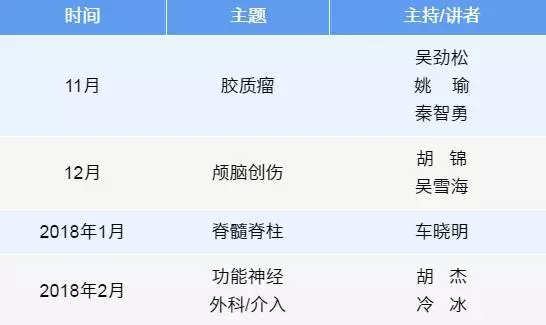

微课预告

注:以下神外微课堂的亚术式专题和主持讲者为截止目前的初步计划,具体安排请以该月发布的微课通知为准。